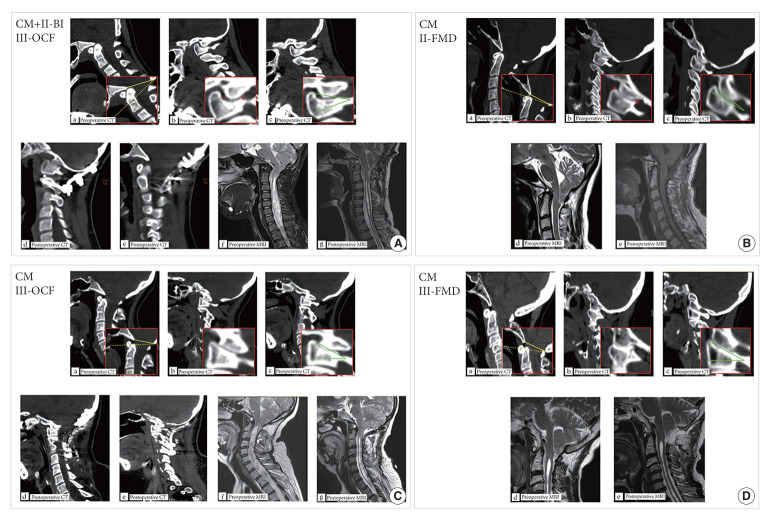

Methods: We retrospectively studied 212 CM patients who underwent foramen magnum decompression (FMD) or combined occipitocervical fusion (OCF). Patients were divided into 4 groups: (1) pure CM with II-AOJ who underwent FMD (CM-II-FMD); (2) pure CM with III-AOJ who underwent FMD+OCF (CM-III-OCF); (3) CM-III-FMD; and (4) CM+ II-BI with III-AOJ who underwent FMD+OCF (BI-III-OCF). Clinical data, including manifestations, imaging findings, surgical details, and neurological assessments, were analyzed at the final follow-up to assess surgical efficacy.

Results: Patients in the BI-III-OCF, CM-III-OCF, and CM-II-FMD groups exhibited a significant improvement in clinical symptoms (pain, sensory disturbances, motor weakness, gait ataxia, and bladder and bowel dysfunction) compared to preoperative levels (p<0.05). Results from the Japanese Orthopaedic Association scale and Neck Disability Index indicated a significant reduction in the degree of neurological impairment within these groups (p<0.05). Furthermore, the Chicago Chiari Outcome Scale scores indicated superior surgical outcomes for patients in these groups. Imaging analyses demonstrated significant reductions in the syringomyelic segment, syringomyelia width, and tonsillar herniation distance among these patients (p<0.05). However, the CM-III-FMD group did not significantly improve in these areas (p>0.05). Postoperative complications occurred in 4.3% of FMD+OCF patients and 3.3% of FMD-only patients.

Conclusion: AOJ morphological types can guide surgical treatment strategies for CM with or without II-BI. FMD alone is suitable for II-AOJ cases, whereas III-AOJ cases should be treated with FMD combined with OCF.